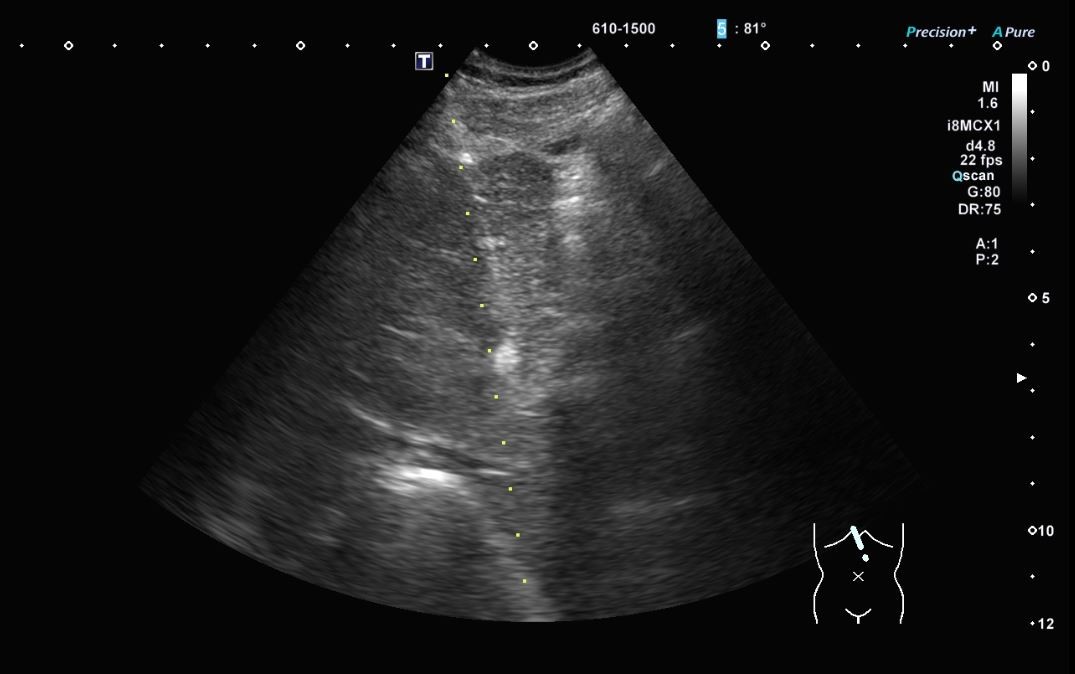

肝疾患の診断・治療も重要です。慢性肝炎では、C型慢性肝炎に対する直接型抗ウイルス薬(DAA)によるIFNフリー抗ウイルス治療、B型慢性肝炎に対する核酸アナログ製剤(エンテカビル・テノホビル)治療の多数の経験があります。最近増えている脂肪性肝炎(SLD: MASH、 MASLD)を含めて、肝臓リハビリテーション、亜鉛補充、栄養療法(NST)、肝臓病教室、市民公開講座を通じて多職種がサポートする体制を構築しています。肝臓がんに対しては進行度や病状に応じて、ラジオ波焼灼療法やマイクロ波焼灼療法、外科手術、肝動脈塞栓化学療法併用、抗がん剤治療を選択しています。特に肝臓がんに対する超音波ガイド下治療では、CTやMRI画像を取り込み超音波画像と同期させ同一画面に表示する機能(Smart Fusion Imaging)を実装し、治療専用の穿刺用マイクロコンベックスプローブにより治療精度の向上を図っています。

最新の超音波装置を駆使し、肝臓繊維化の評価や、肝障害の精密検査として超音波ガイド下肝生検、急性胆嚢炎に対する胆嚢ドレナージ術も多くの実績があります。

腹部臓器(肝臓/胆嚢/膵臓/脾臓/腎臓/膀胱/尿管/消化管等)疾患の診断・治療に用います。

肝臓の線維化の評価にSWE(Shear wave Elastography)、脂肪化の評価にATI(Attenuation imaging)を測定しています。

腹部超音波検査2724例

肝腫瘍ラジオ波焼灼/マイクロ波凝固療法18例

肝生検23例